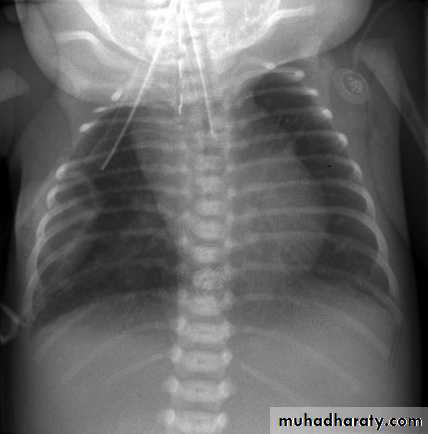

• ATRESIA:

• - Complete blockage of the lumen .

• - The diagnosis is suggested after birth by in ability of infant to feed or by choking during swallowing .

• - The blocked segment is mostly seen at level of thoracic inlet